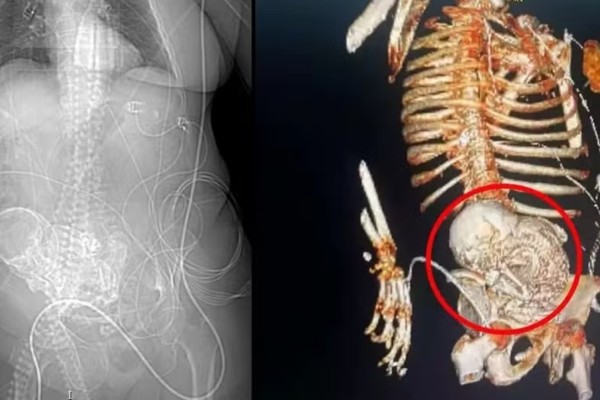

“Bebê de pedra”: Idosa descobre feto calcificado que carregou por 56 anos